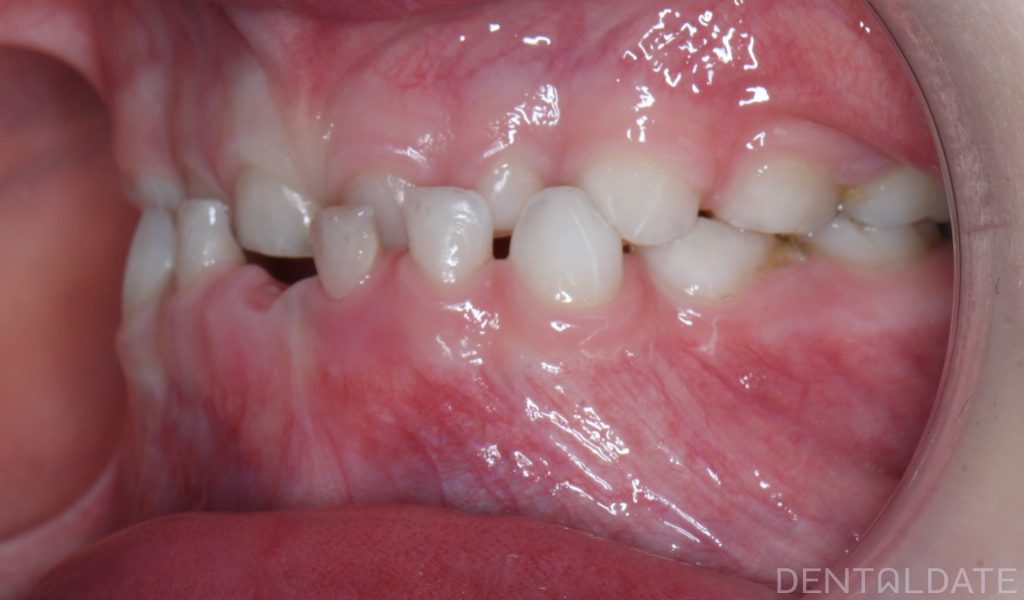

The patient’s mother came in for a consultation, reporting that her child was experiencing difficulty chewing and rarely smiled.

A key goal of children orthodontic treatment is to normalize physiological growth and development.